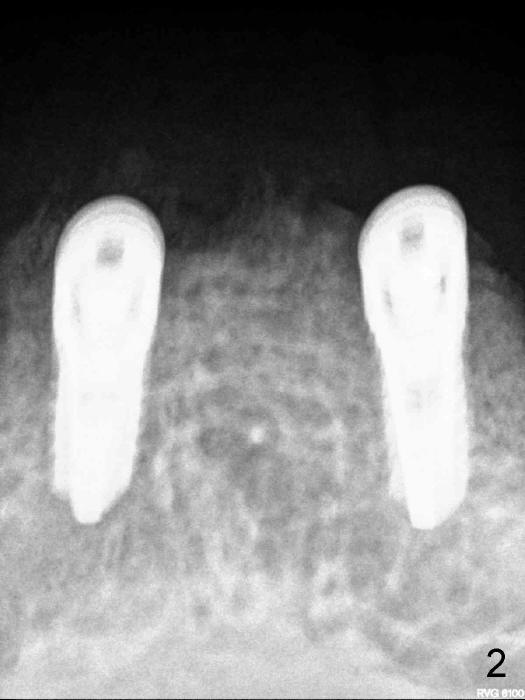

Here is another case: female, 68yrs, two implants supported overdenture, panorex was preop (Fig.1), pa with two implants was taken one week after implant insertion (Fig.2), another pa with some shadow was taken one month after surgery (Fig.3). Now presented fistula on the alveolar ridge. I have not idea what is going on? Do you have any idea/what causes it?  It happened couple cases already.  I handled these kinds of cases: take out implants, wait for healing and place implants again.